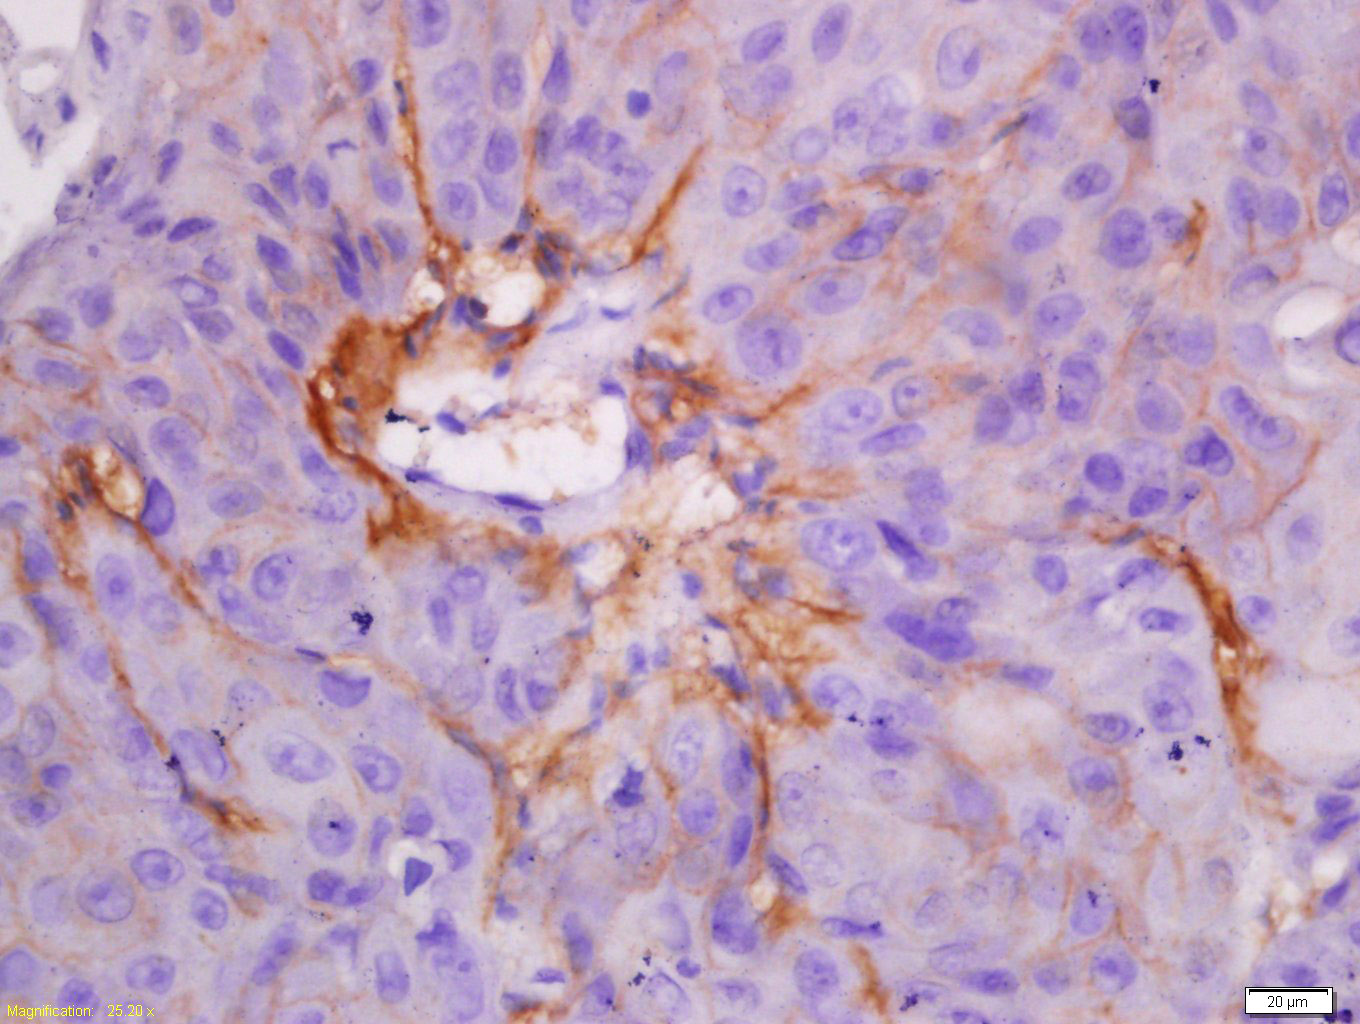

Tissue/cell: human lung carcinoma; 4% Paraformaldehyde-fixed and paraffin-embedded; Antigen retrieval: citrate buffer ( 0.01M, pH 6.0 ), Boiling bathing for 15min; Block endogenous peroxidase by 3% Hydrogen peroxide for 30min; Blocking buffer (normal goat serum,C-0005) at 37℃ for 20 min; Incubation: Anti-CK7 Polyclonal Antibody, Unconjugated(bs-1610R) 1:200, overnight at 4°C, followed by conjugation to the secondary antibody(SP-0023) and DAB(C-0010) staining